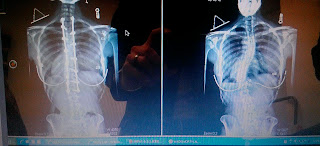

| There it is. Can you believe it! Still crazy to me. |

Yesterday I had the opportunity to visit with my doctor and discus further options on my recovery. I was a bit nervous especially after my last appointment and finding that my back was now curving the wrong way. We were all glued on the x-rays as Doctor Klatt examined closely. He explained that I was fully fussed and the back was as straight as it will ever get, and that the lower curvature looked better from the last time. I was on track. I asked questions about some of the pain I have been going through and he explained that it will take time for a person as active as I am to get use to the hardware. We discussed other topics of the back, such as, how my body was reacting through therapy and other activities that I feel a bit limited with. Then as he was explaining the stages I was going through he said, “You may do anything now,” I stopped him and knowing my curiosity I asked, “What do you mean by anything?” He jokingly answered, “You can go ride a bull and be just fine; though I wouldn’t suggest it.” So instantly I asked the question I have been waiting to ask for 7 months, “Can I start dancing again?” He smiled and said yes, I turned to Enoch and said, “You heard it right out the doctors mouth.”

| It’s so CRAZY to see how far I have come. My body is all new to me and I can’t wait to find out what it does next. |